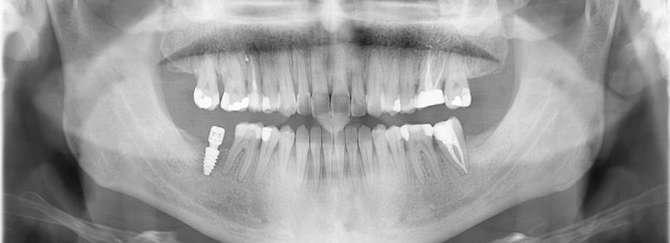

3. Análisis radiográfico y tomográfico (Ilustración 4):

 Constricción maxilar con deficiencia transversal

> 5 mm.

 Clase III esquelética.

 Patrón esquelético hiperdivergente con el plano oclusal mandibular compensado con rotación anti-horaria.

 Sutura palatina media parcialmente osificada (8) (9).

 Posición de terceros molares no favorable, por lo que se recomendó extracción.

Ilustración 4. Registros radiográficos iniciales de estudio.